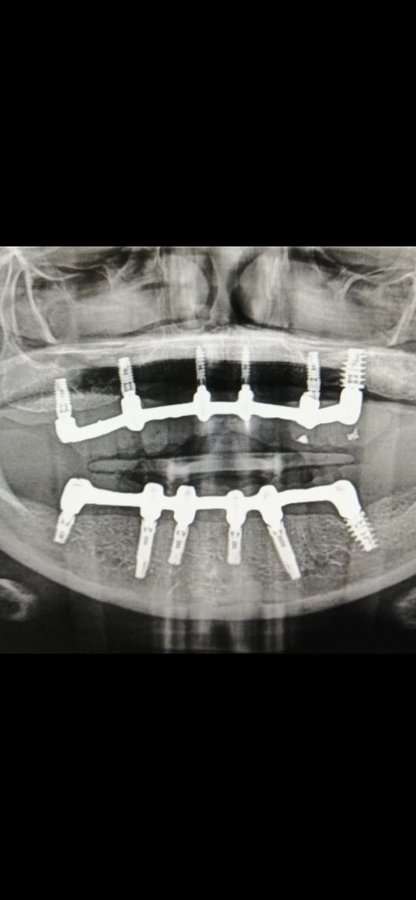

About Live Implants Nicaragua Virgil Mongalo DMD is a dental implant surgeon, past professor of implant surgeries at the University of Miami and the University of Florida has opened a surgical implant center in Managua. This is a state of the art facility consisting of equipped with Ct-scan, 3D Printer, zirconia milling machine, 8 surgical rooms, and USA sterilization controls. His team consists of implant surgeries professor accredited... (Show more)